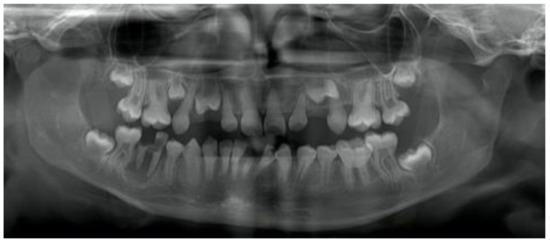

3.1. Dentinogenesis Imperfecta

4.1. Dentinogenesis Imperfecta